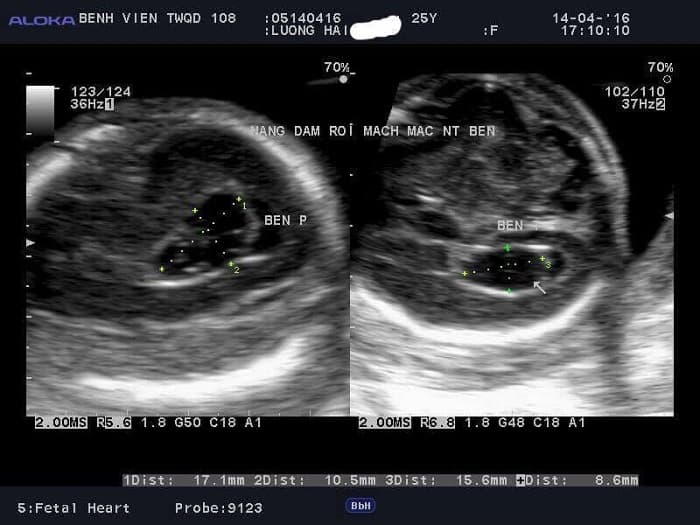

Nang đám rối mạch mạc bản chất là một không gian nhỏ giữa các đám rối màng mạch chứa chất lỏng trong suốt (chất lỏng này được gọi là dịch não tủy) và những mảnh vỡ tế bào trong màng mạch tâm thất của não thai nhi.nang đám rối mạch mạc 2 bên

Nang đám rối mạch mạc được phát hiện trong quá trình siêu âm

Kích thước các nang đám rối mạch mạc rất đa dạng tùy mức độ phát triển của nang đám rối. Vị trí xuất hiện của các nang này có thể ở một bên hoặc hai bên não thất. Số lượng nang cũng có thể là một nang hoặc đa nang. Tuy nhiên, các nang này ở giai đoạn sớm rất dễ nhầm lẫn với các đám rối màng mạch cho không đồng nhất. Chính vì vậy, trong từng giai đoạn của thai nhi, có thể phát hiện được chính xác các nang đám rối mạch mạc thì kích thước tối thiểu cần đạt như sau:nang đám rối mạch mạc não thất bên trái

- Giai đoạn từ 13 tuần tuổi đến 21 tuần tuổi: kích thước nang đạt 2,5 mm

- Giai đoạn từ 22 đến 38 tuần tuổi: kích thước nang từ 2mm